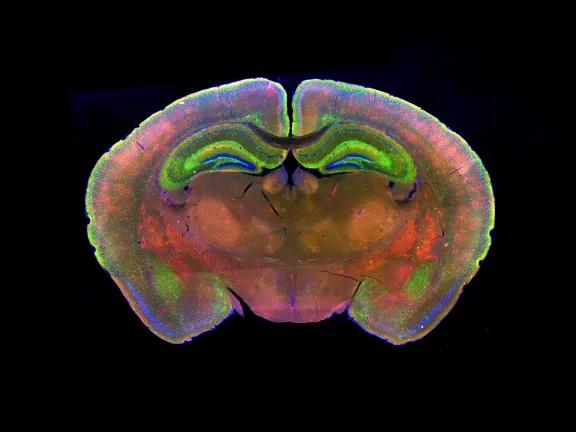

Quand la biologie s'invite dans nos choix

Nous pensons être maîtres de nos choix mais les neurosciences montrent...